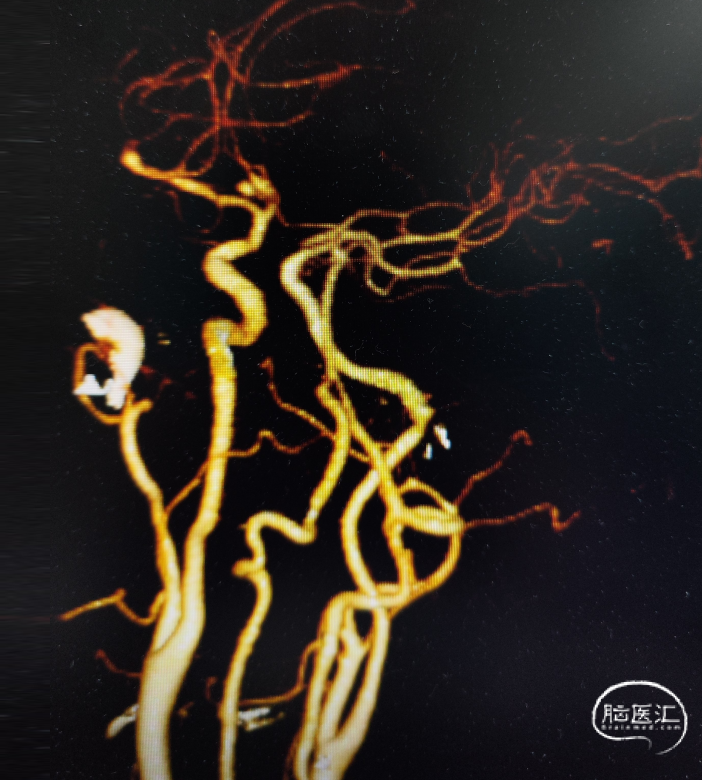

头颅CT显示:额叶蛛网膜下腔出血。

完善头颅CTA显示:前交通动脉瘤、左侧大脑中M1段末端动脉瘤。

DSA造影确认前交通动脉瘤、左侧大脑中M1段分叉部动脉瘤。

前交通动脉瘤5.94mm*4.12mm,瘤体呈分叶状。

患者右侧大脑前发育纤细;后循环血管无明显异常。